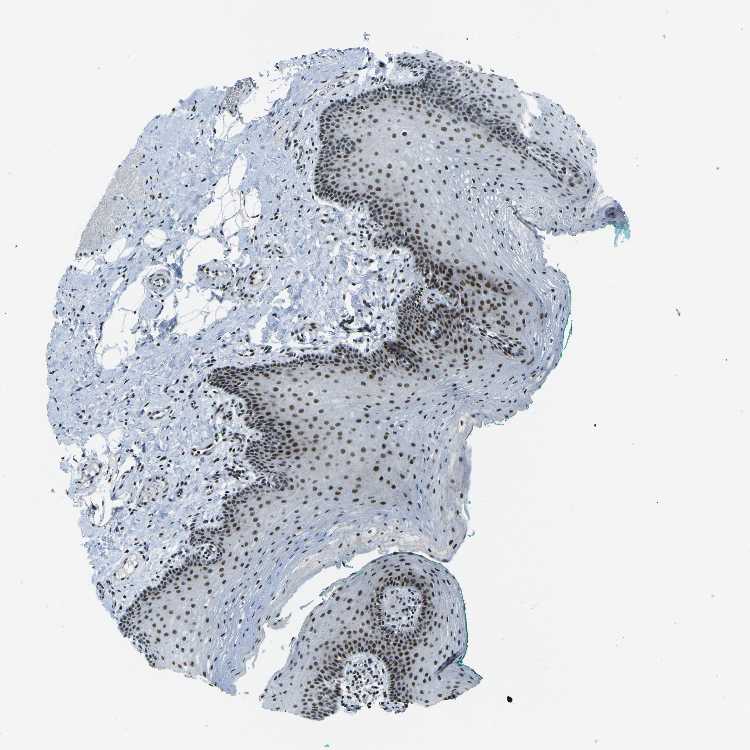

TISSUE PRIMARY DATA ORAL MUCOSA Show tissue menu

Oral mucosa

ORAL MUCOSA - Antibody stainingi

Antibody staining in the annotated cell types in the current human tissue is reported as not detected, low, medium, or high, based on conventional immunohistochemistry profiling in selected tissues. This score is based on the combination of the staining intensity and fraction of stained cells.

Each image is clickable and will lead to virtual microscopy that enables deeper exploration of all samples and also displays staining intensity scores, fraction scores and subcellular localization as well as patient and tissue information for each sample.

Antibody HPA019703Antibody CAB016547

Squamous epithelial cells HighHigh